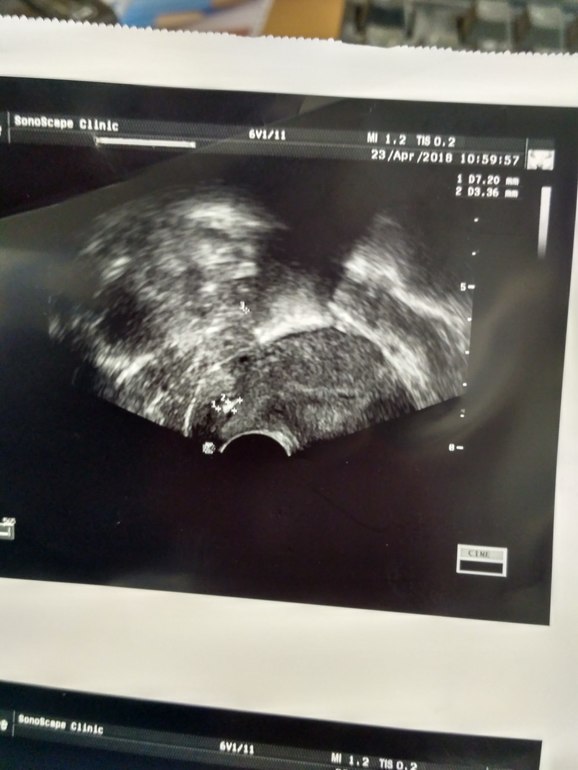

Добрый день, девочки. Кто сталкивался с ним? Как удаляли? Восстанавливались? Я надеялась что это складка,но похоже полип. Но не видно не ножки,не кровотока. Предлагают удалять. А вдруг это складка просто. В общем поделитесь опытом. Мой полип

у меня 3,5*7. Просто не факт что это он. Кровотока нет, ножки тоже. Поеду 26 на консультацию еще к одному врачу. Легких родов вам! ))))